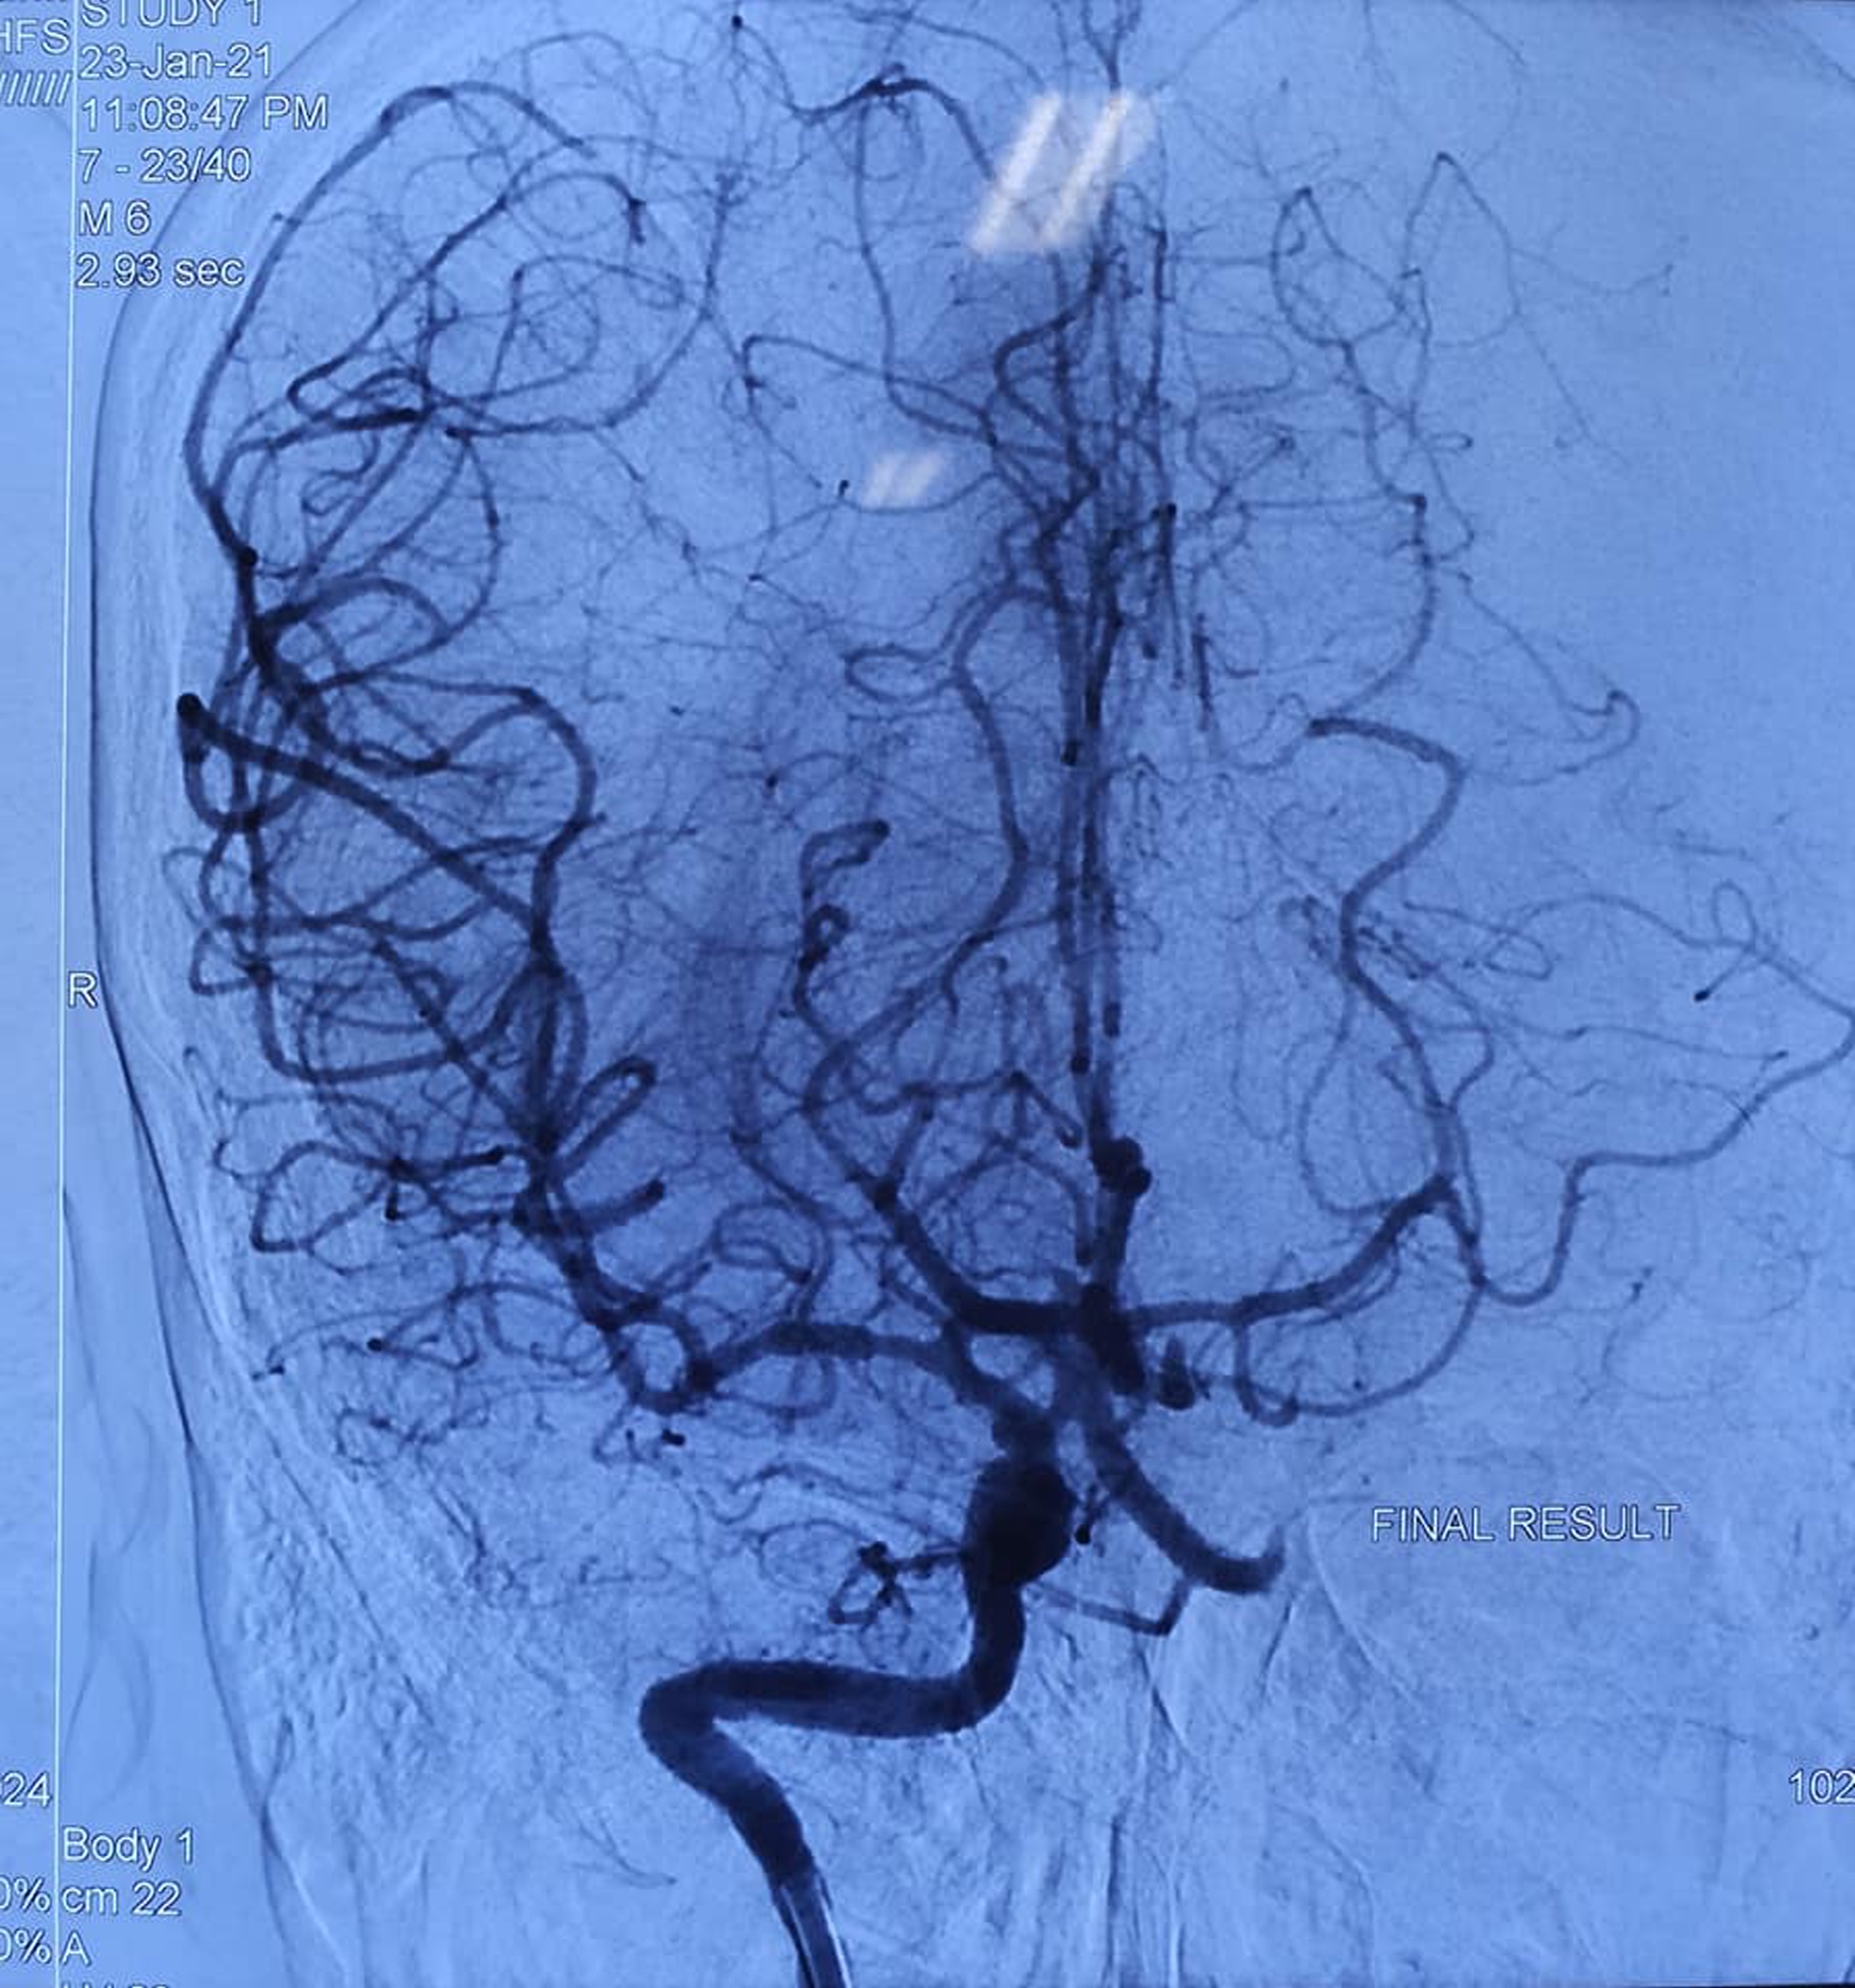

Hình ảnh mạch máu bị tắc qua phim chụp của bệnh nhân

Bệnh nhân được chẩn đoán bị tắc một đoạn mạch mãu não khá lớn. Do đó, các bác sĩ đã can thiệp bằng thuốc tiêu huyết khối và lấy huyết khối bằng dụng cụ để tái thông mạch máu cho bệnh nhân. Đến nay, bệnh nhân đã hồi phục hoàn toàn, có thể tiếp tục công việc và cuộc sống bình thường sau khi xuất viện.